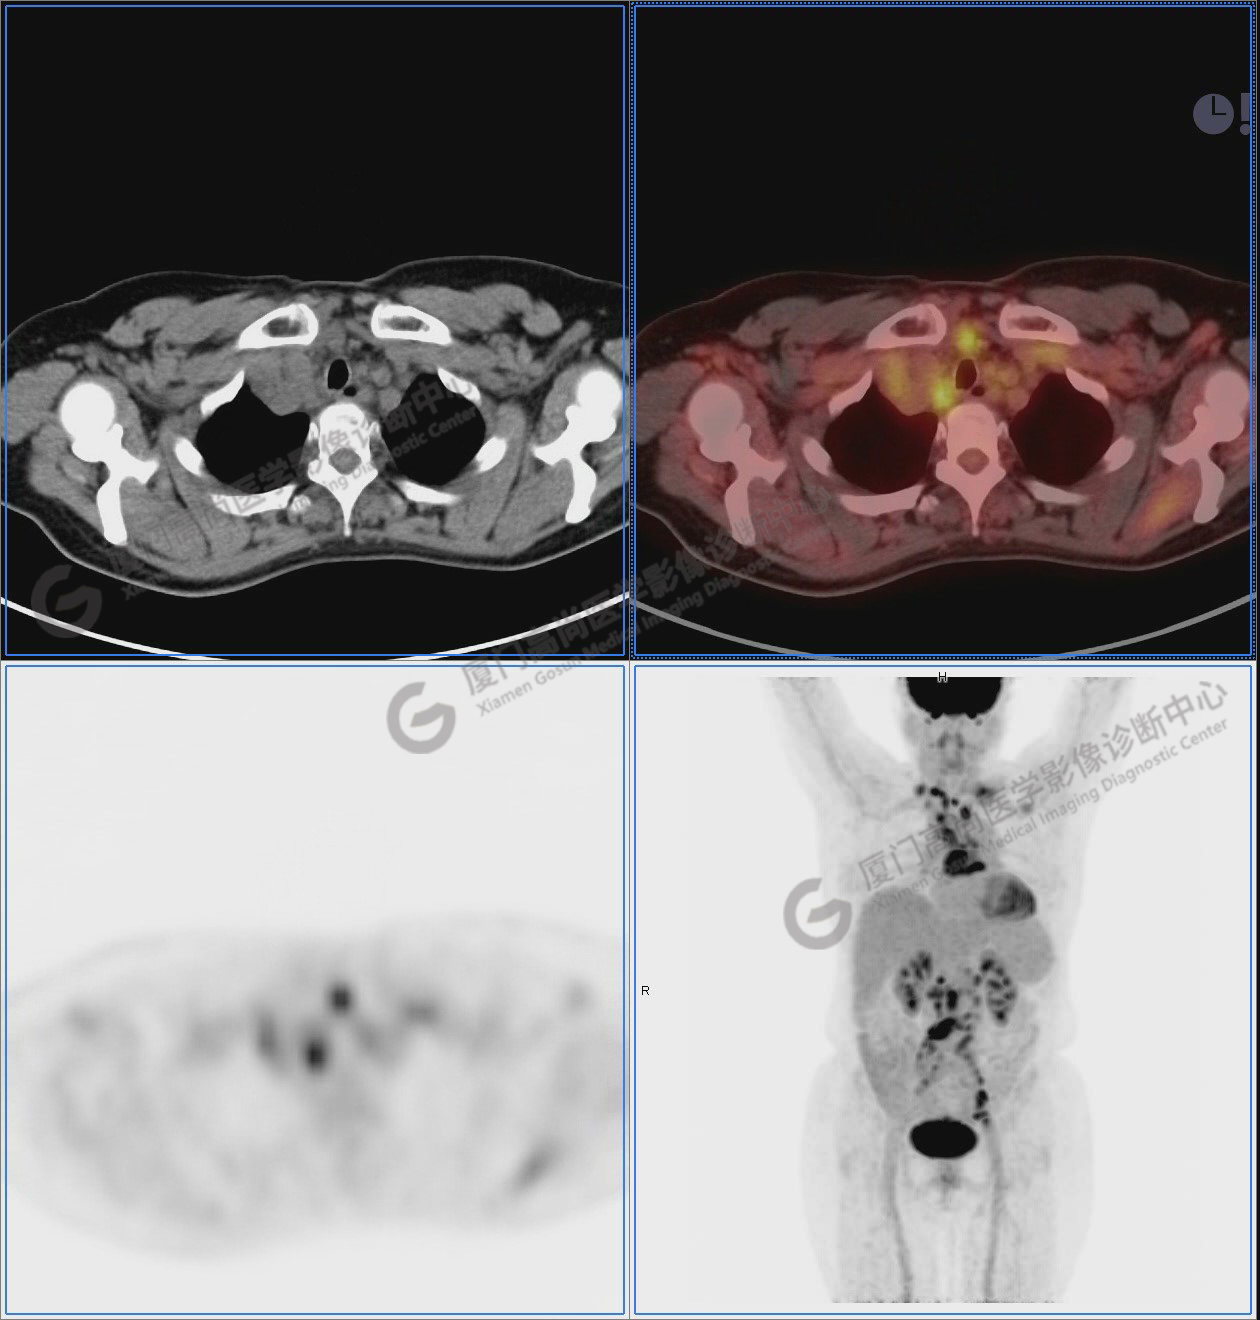

圖1:PET/CT全身圖像

圖2-9:雙側(cè)鎖骨區(qū)、縱隔、右側(cè)內(nèi)乳區(qū)、腸系膜緣、腹膜后、雙側(cè)髂血管旁及盆腔多發(fā)腫大淋巴結(jié)影,代謝不同程度增高,考慮為轉(zhuǎn)移。

圖2